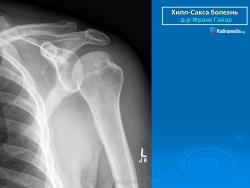

На рентгенограмме плечевого сустава определяется умеренный остеопороз головки плечевой кости. Иногда на ее задненаружной поверхности позади вершины большого бугорка выявляется вдавленный дефект (повреждение Хилл-Сакса). Дефект четко виден на рентгенограмме в аксиальной проекции. Аналогичный, но менее выраженный дефект может быть выявлен в зоне передненаружного края суставной впадины лопатки. Также в диагностике причин привычного вывиха плеча помогает МРТ исследование.

рентгенограмма плечевого сустава. Повреждение Хилл-Сакса и сопутствующий кальциноз сухожилий вращательной манжеты